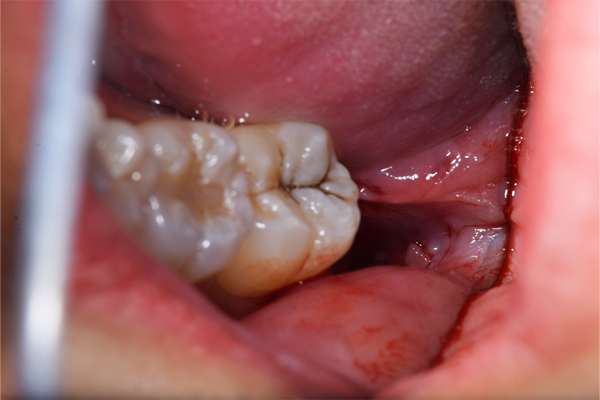

下顎の親知らずの抜歯のBefore/Afterになります。歯ぐきの中に埋まっていましたが、歯ぐきを切ることなく、低侵襲に手術を終えられました。抜歯時間は10分です。下顎は斜めにはえている親知らずを抜く場合は歯ぐきを切ったり、親知らずの周りの骨を削ることが多いので、術後1週間くらい腫れることが多いです。

また、下顎は、親知らずの根の先端が顎の骨のなかにある神経と近いことが多いです。神経と根の先がくっついている場合は抜く際に注意が必要となります。抜歯費用は約7,500円(保険適応、CT撮影込)です。